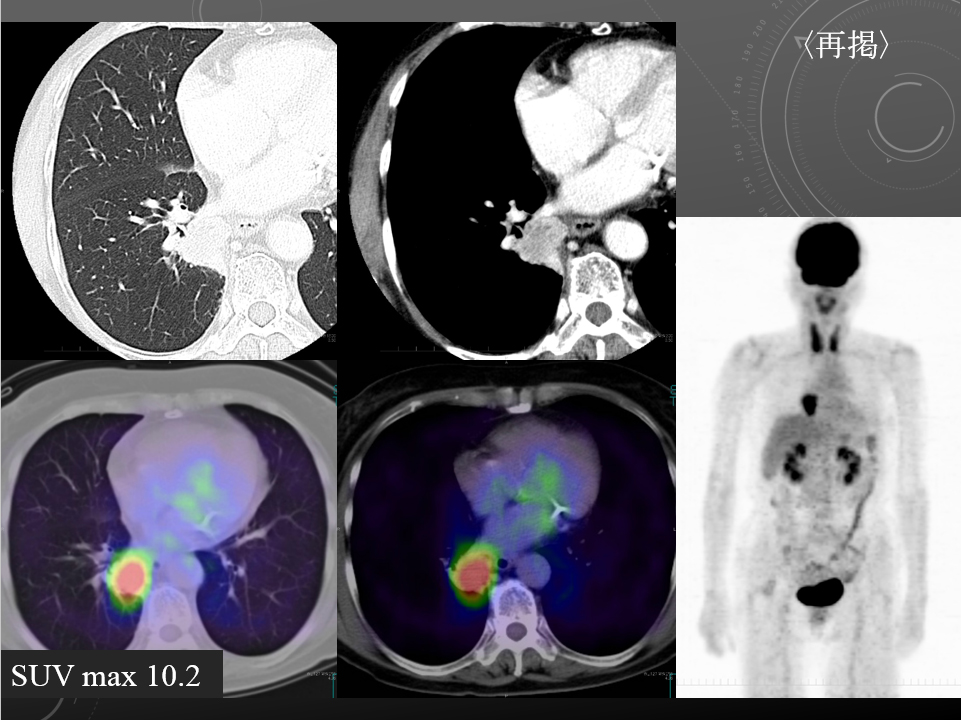

68F CEA 高値精査。消化器内科依頼。既往に脳梗塞、心筋梗塞、胃ポリープあり。

右肺下葉腺癌。

右肺下葉の縦隔側には最大径31mm大の不整形な腫瘤性病変を認めます。表面には部分的にspicula所見が見られ、胸膜に広汎に隣接するように存在しています。内部は辺縁を中心に淡い造影効果を呈しています。原発性肺癌病巣が疑われます。肺門部にはリンパ節腫大像が見られますが、縦隔領域に明らかに有意なリンパ節腫大は指摘出来ません。

左肺下葉に末梢側には淡い濃度上昇所見が見られ、GGO病変が疑われます。この他、肺野に明らかな腫瘤性病変は指摘できません。

・Lung cancer s/o

SUVmaxは10.2

右肺下葉内側の腫瘤に一致して異常集積を認める。